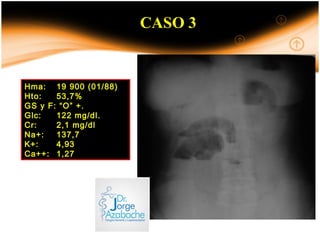

CASO 3

Hma: 19 900 (01/88)

Hto: 53,7%

GS y F: “O” +.

Glc: 122 mg/dl.

Cr: 2,1 mg/dl

Na+: 137,7

K+: 4,93

Ca++: 1,27